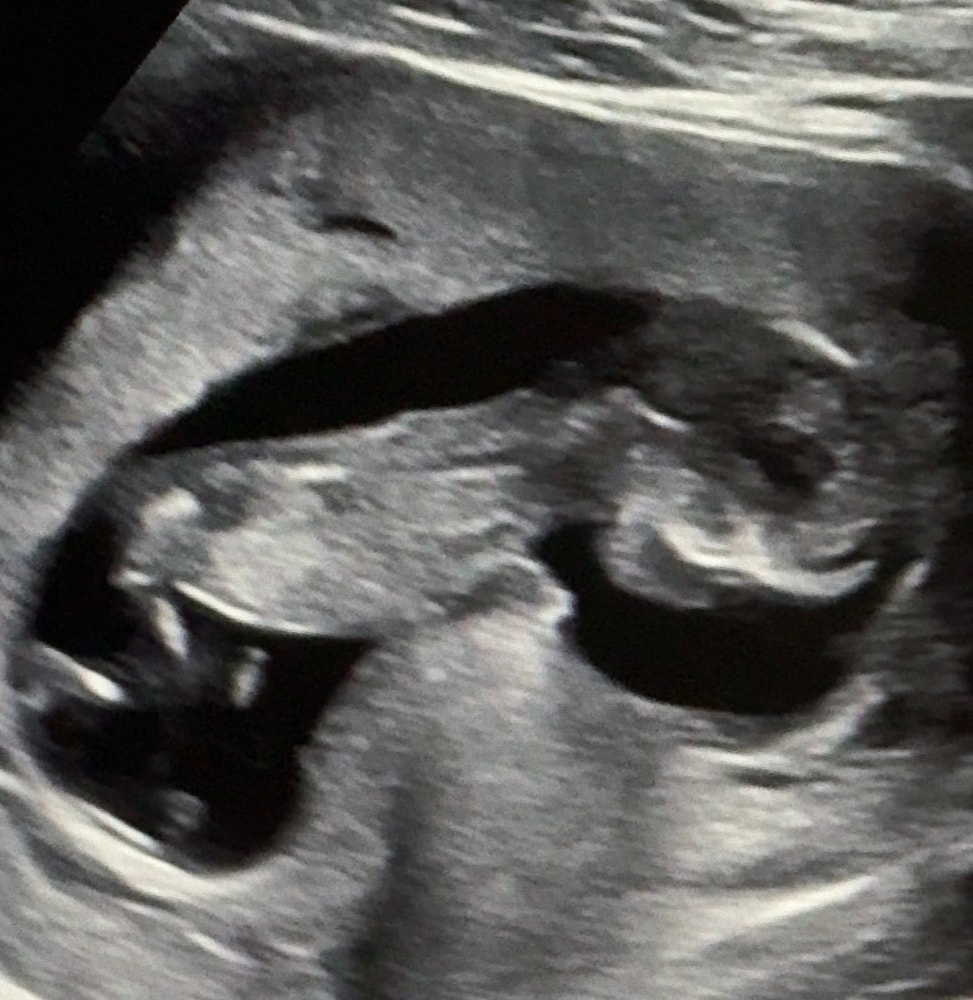

Девчонки, пропала что-то я, давно не заходила. А все потому что очень переболели с мужем. Врачи говорят была какая то корона только кишечная. Переболели 3 недели и вот по тихоньку идем на поправку. Но суть не в этом, сегодня были на узи, а точнее, на втором скрининге